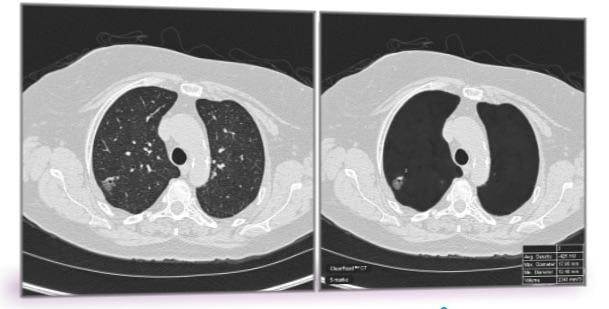

To address the problem of false positives in lung cancer screening, Peikert and Fabien Maldonado, M.D., from Vanderbilt University, along with their collaborators, used a radiomics approach to analyze the CT images of all lung cancers diagnosed as part of the National Lung Cancer Screening Trial. Radiomics is a field of medicine that involves extracting large amounts of quantitative data from medical images and using computer programs to identify disease characteristics that cannot be seen by the naked eye.

Researchers tested a set of 57 variables for volume, nodule density, shape, nodule surface characteristics and texture of the surrounding lung tissue. They identified eight variables which enabled them to distinguish a benign nodule from a cancerous nodule. None of the eight variables were directly linked to nodule size and the researchers did not include any demographic variables such as age, smoking status and prior cancer history as part of their testing.